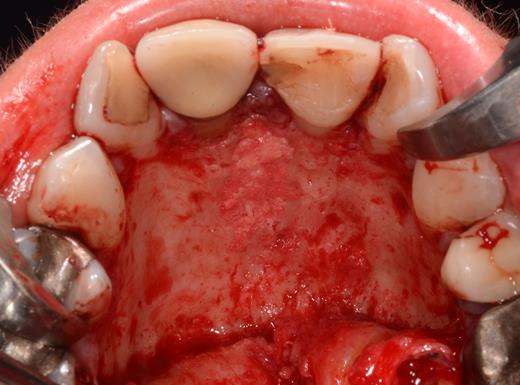

After a sulcular incision on the palatal side from teeth 15 to 25 and an incision in the midline of the palate omitting the incisive papilla and the two orifices of the NPD, two full-thickness mucoperiosteal flaps were raised. Thereafter, the incisive papilla and the whole contents of the incisive canal were enucleated (Figs 4–6). The bony incisive canal was filled with autologous bone harvested from the palatal region (bone scraper) (Fig. 7). A tension-free primary wound closure was achieved by moving the palatal flaps to the midline using single button and interdental vertical mattress sutures (Monocryl 4-0, Ethicon, Johnson & Johnson, USA) (Fig. 8). To avoid wound dehiscence and hematoma, an iodoforme gauze and a palatal plate were applied (Fig. 9). The patient was instructed to rinse three times a day with 0.1% chlorhexidine (formula hospitalis) for 2 weeks postoperatively. Sutures were removed after 14 days.

Situation after removal of the entire soft tissue contents of the incisive canal.